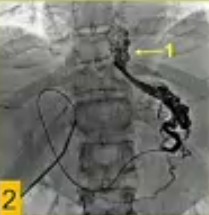

![]() ![]() US引导下经皮进入门静脉分支(瘤栓远端周围静脉),随后在瘤栓“上方”进行门静脉造影;

由于导管通过瘤栓,在血栓“下方”进行门静脉造影。

门静脉手术细节:使用5或8F直径的双极射频装置(HabibTM EndoHPB, EMcision Ltd., London, UK),施加10-15瓦的功率,持续2分钟,该装置通过导管定位到PV血栓中

技术上的成功被定义为重新建立肝壁血流进入肝内PV分支的通畅,重新连接主PV或PV汇合处,以重建中断的门静脉血流进入整个肝脏或肝叶/节段。